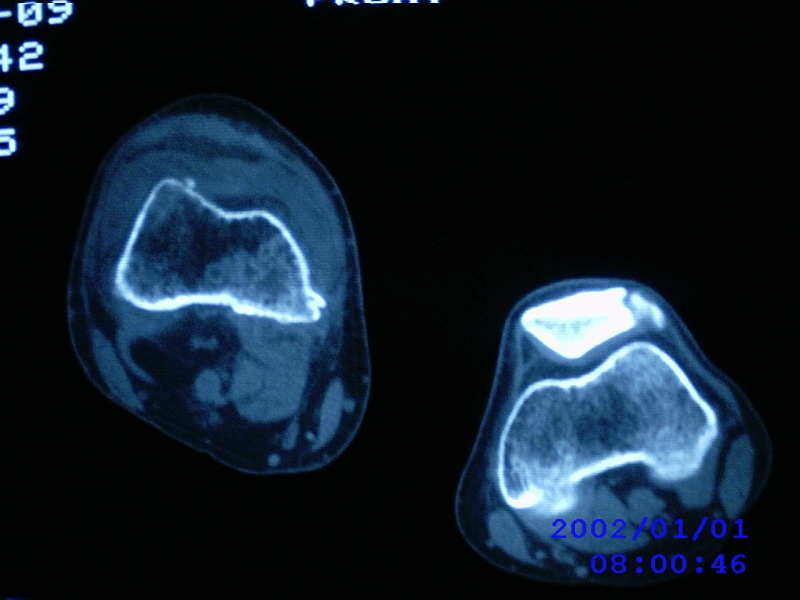

患者,男性,57岁,右侧膝关节疼痛伴肿脹10余年,加重一个月。

关节积液,关节间隙变窄,边缘骨破坏。考虑膝关节tb

关节积液,关节间隙变窄,骨质疏松,多发骨破坏,边缘轻度硬化,近端胫腓骨髓腔软组织充填,患者病史较长,支持考虑结核

有皮质的破坏~有死骨存在

多发骨破坏,骨质疏松,关节积液。考虑右膝关节结核。